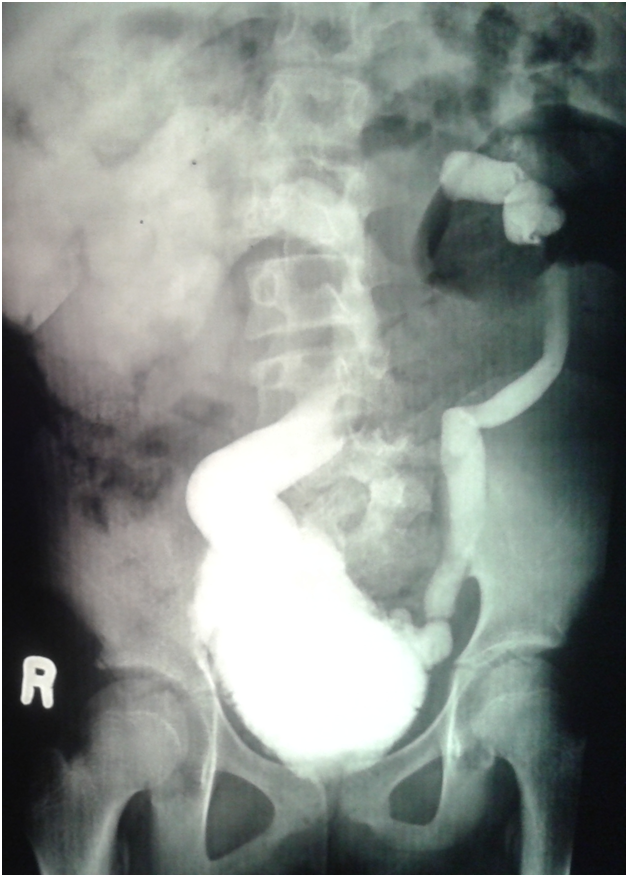

An eleven year old girl was presented to with chronic constipation, persistent dribbling of urine and recurrent urinary tract infections since early childhood. She received treatment by local physicians but remained without proper response. On examination, child was a febrile and her bladder was palpable. Her buttocks were flattened (Figure 1) and external genitalia were wet and excoriated. Anal tone was found decreased on digital rectal examination and the rectum was loaded with hard stool. No definite neurological deficit was found. She was catheterised and stool evacuated with per rectal enema. Her blood analysis showed low haemoglobin (8.1gm %), leucocytosis and raised serum creatinine level (2.2mg %). Urine analysis showed plenty of pus cells and growth of E. coli. Ultrasonography suggested bilateral hydro uretoronephrosis (rt>>lt) with loss of cortico medullary differentiation on right kidney and thickened irregular bladder with significant post void residual urine. Tc-99m DTPA renogram shows poorly functioning right kidney and satisfactorily functioning left kidney. Complete sacral agenesis, 5th lumbar vertebral atrophy and scoliosis with convexity towards right side seen in the control film (Figure 2) while neurogenic bladder with bilateral grade V vesico- ureteric reflux revealed on Voiding phase cystourethrogram (Figure 3). Child was further evaluated with urodynamic study, which suggested an overactive bladder in filling phase (Figure 4). Repeat blood analysis shows (Figure 4) normalisation of serum creatinine (1.2mg %). Her catheter has been removed and she has been placed on self clean intermittent catheterisation along with anti cholinergic (oxy butinine 5mg/daily) and laxative.

Figure 2 Complete Sacral agenesis, 5th lumbar vertebral atrophy.

Figure 2a Showing bilateral grade V vesico- ureteric reflux.

Figure 3 Complete Sacral agenesis, 5th lumbar vertebral atrophy